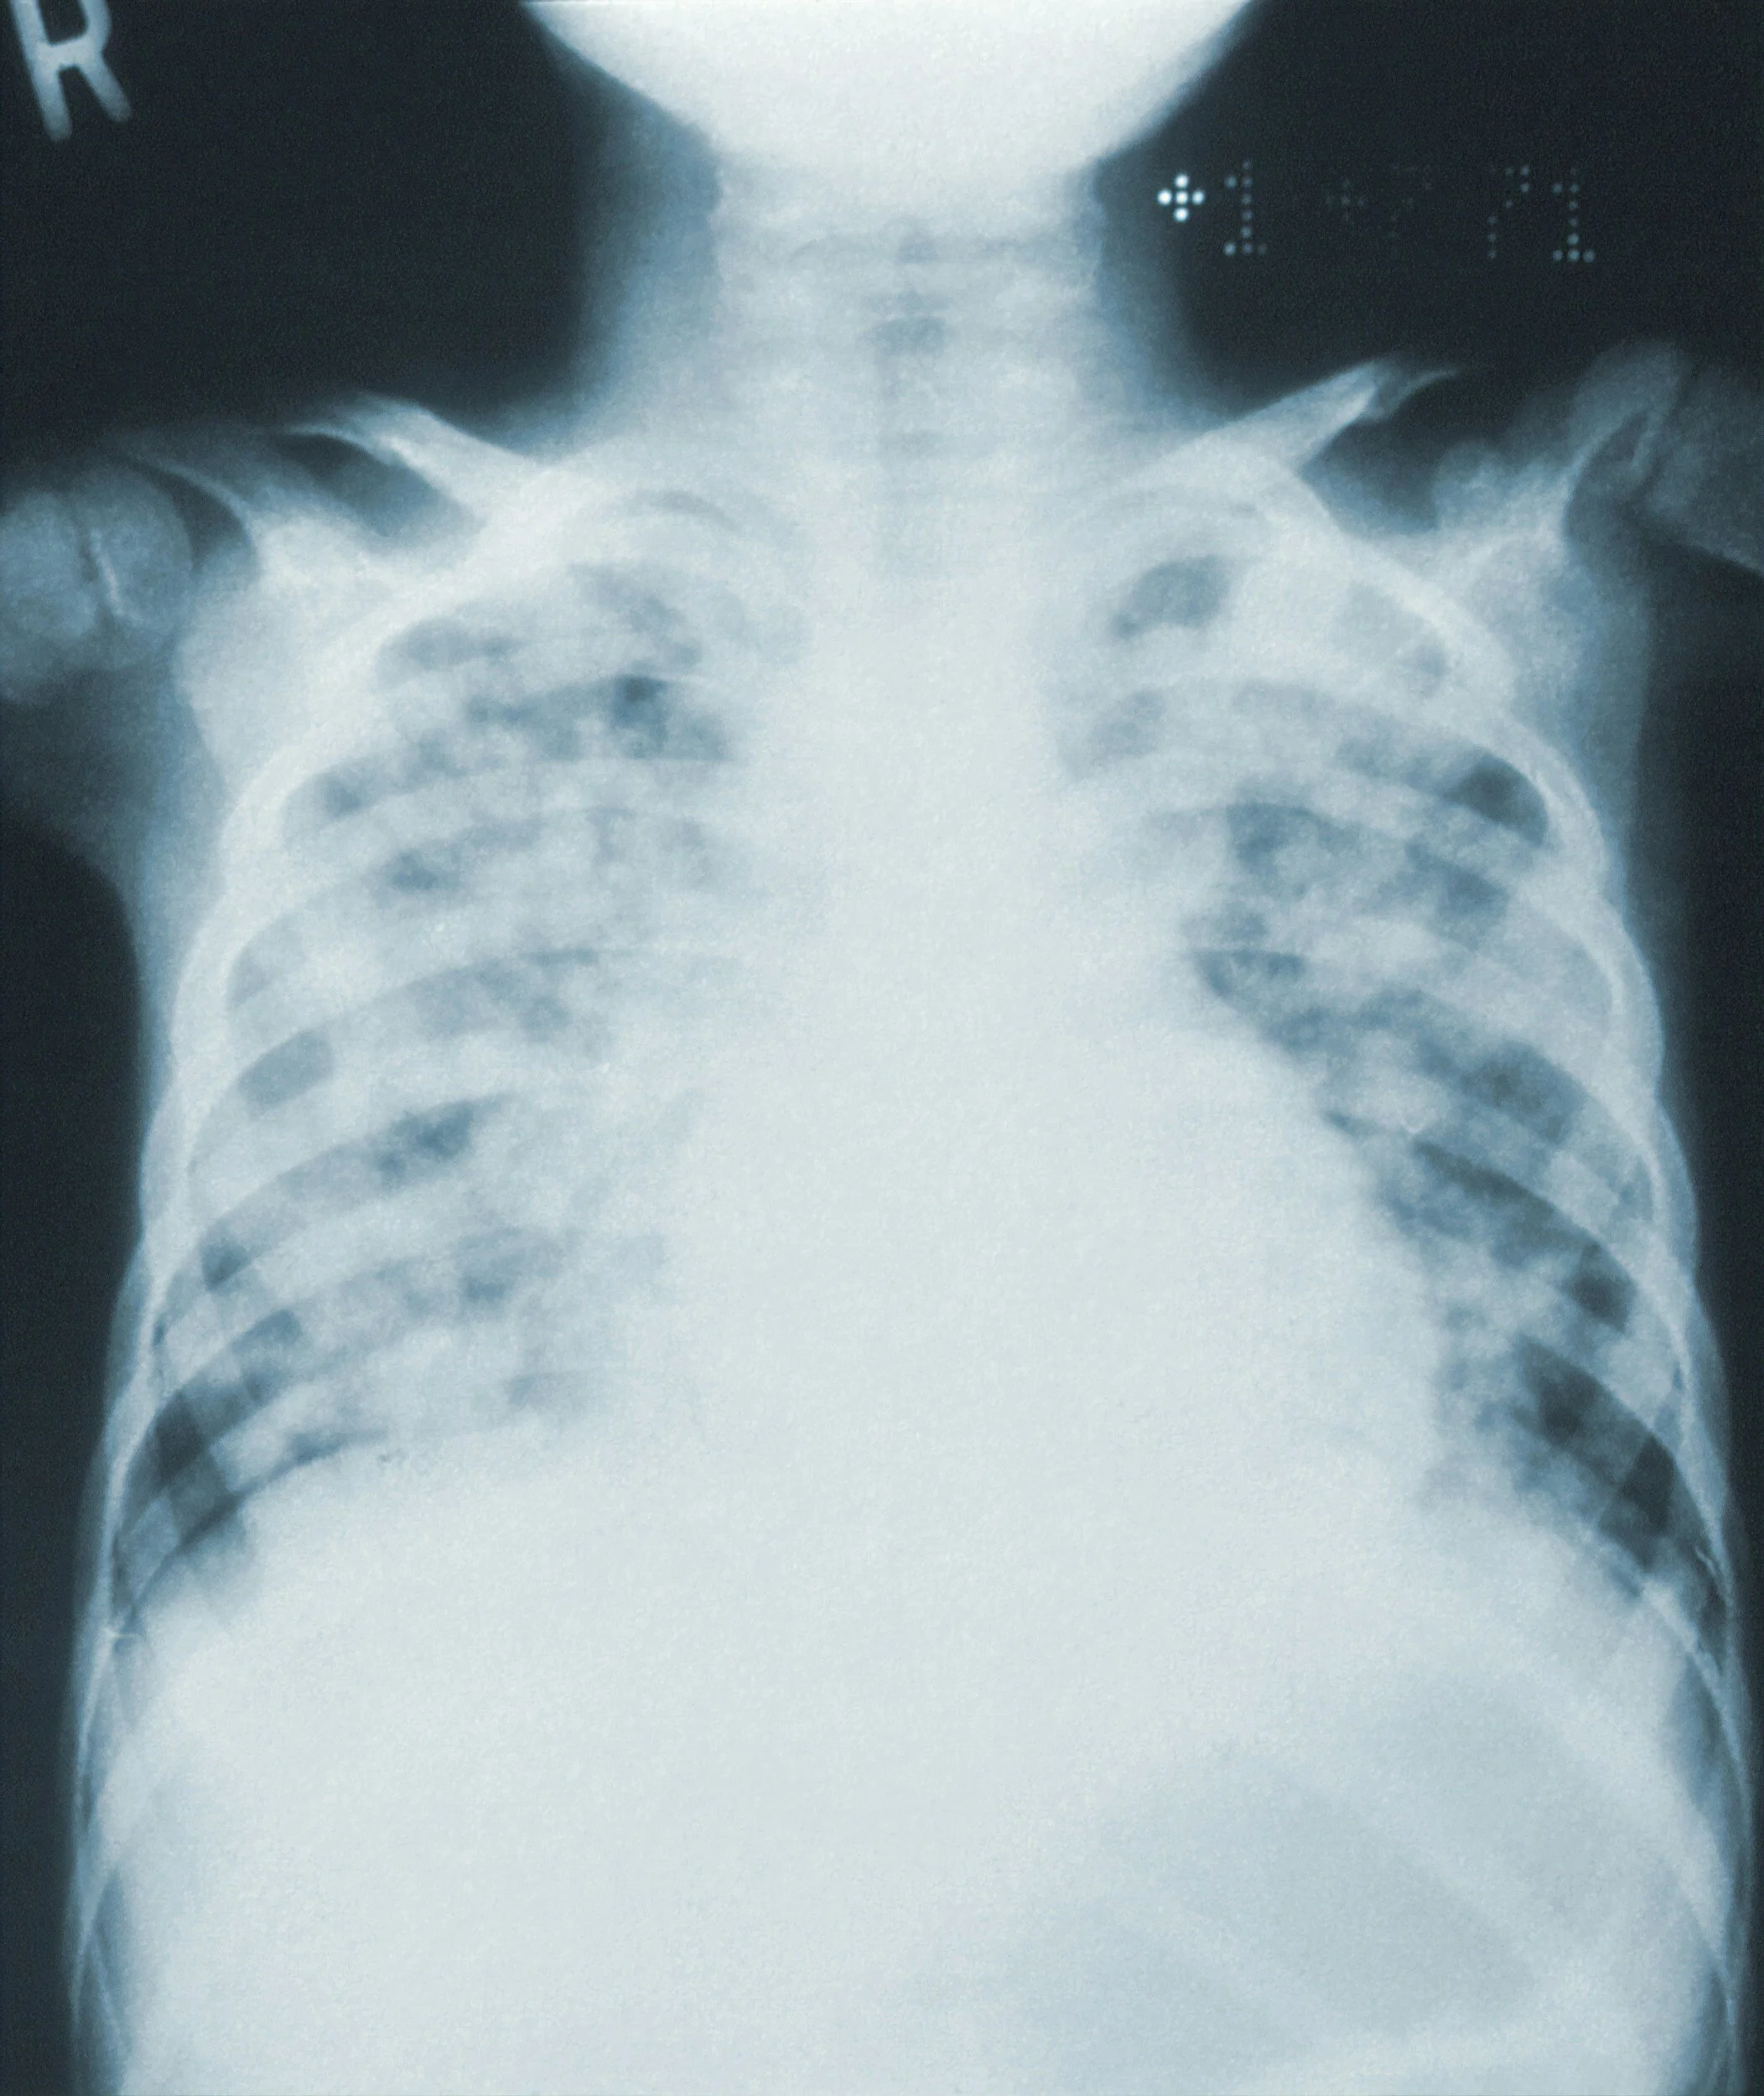

• Pneumonia, probably aspiration, as evidenced by fever, cough, shortness of breath, elevated WBCs, and RLL infiltrate. Was known to have vomited in NH two nights prior. Being treated with antibiotics and supplemental oxygen.